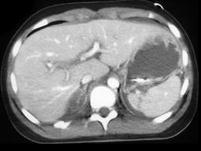

问题 男,32岁,有外伤史,请根据所示图像,选择最可能诊断 ( )

选项 A、右肾挫伤合并右侧肾上腺外伤性出血 B、右肾裂伤合并右侧肾上腺外伤性出血 C、右肾裂伤 D、右侧肾上腺外伤性出血 E、右肾挫伤

答案 B